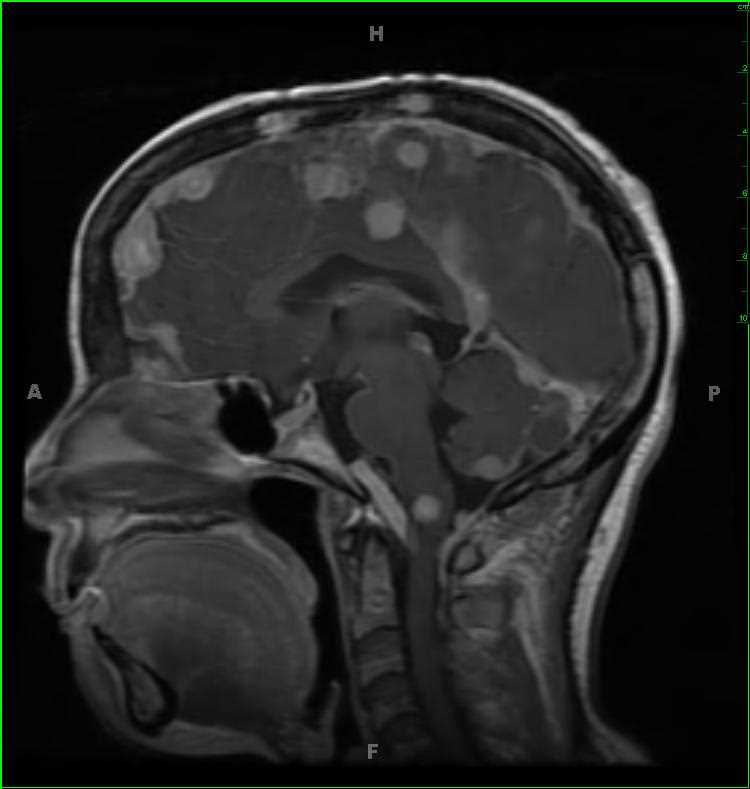

45-year-old female with chronic headaches. There is a well circumscribed, solid and cystic, T1-hypointense, T2/FLAIR-hyperintense, enhancing mass with increased blood volume centered on the foramen of Magendie. The mass enlarges the foramen spilling into both the cisterna magna and fourth ventricle. The differential includes ependymoma, subependymoma, choroid plexus papilloma, meningioma and metastatic disease, given the patients age. This was an anaplastic ependymoma. Ependymomas represent slow growing tumors of the ependymal cells. 2/3 are infratentorial with most centered in the fourth ventricle. Calcifications are common, and cysts and/or hemorrhage may be present. Despite the tumor having low cellularity, ADC values are typically low.